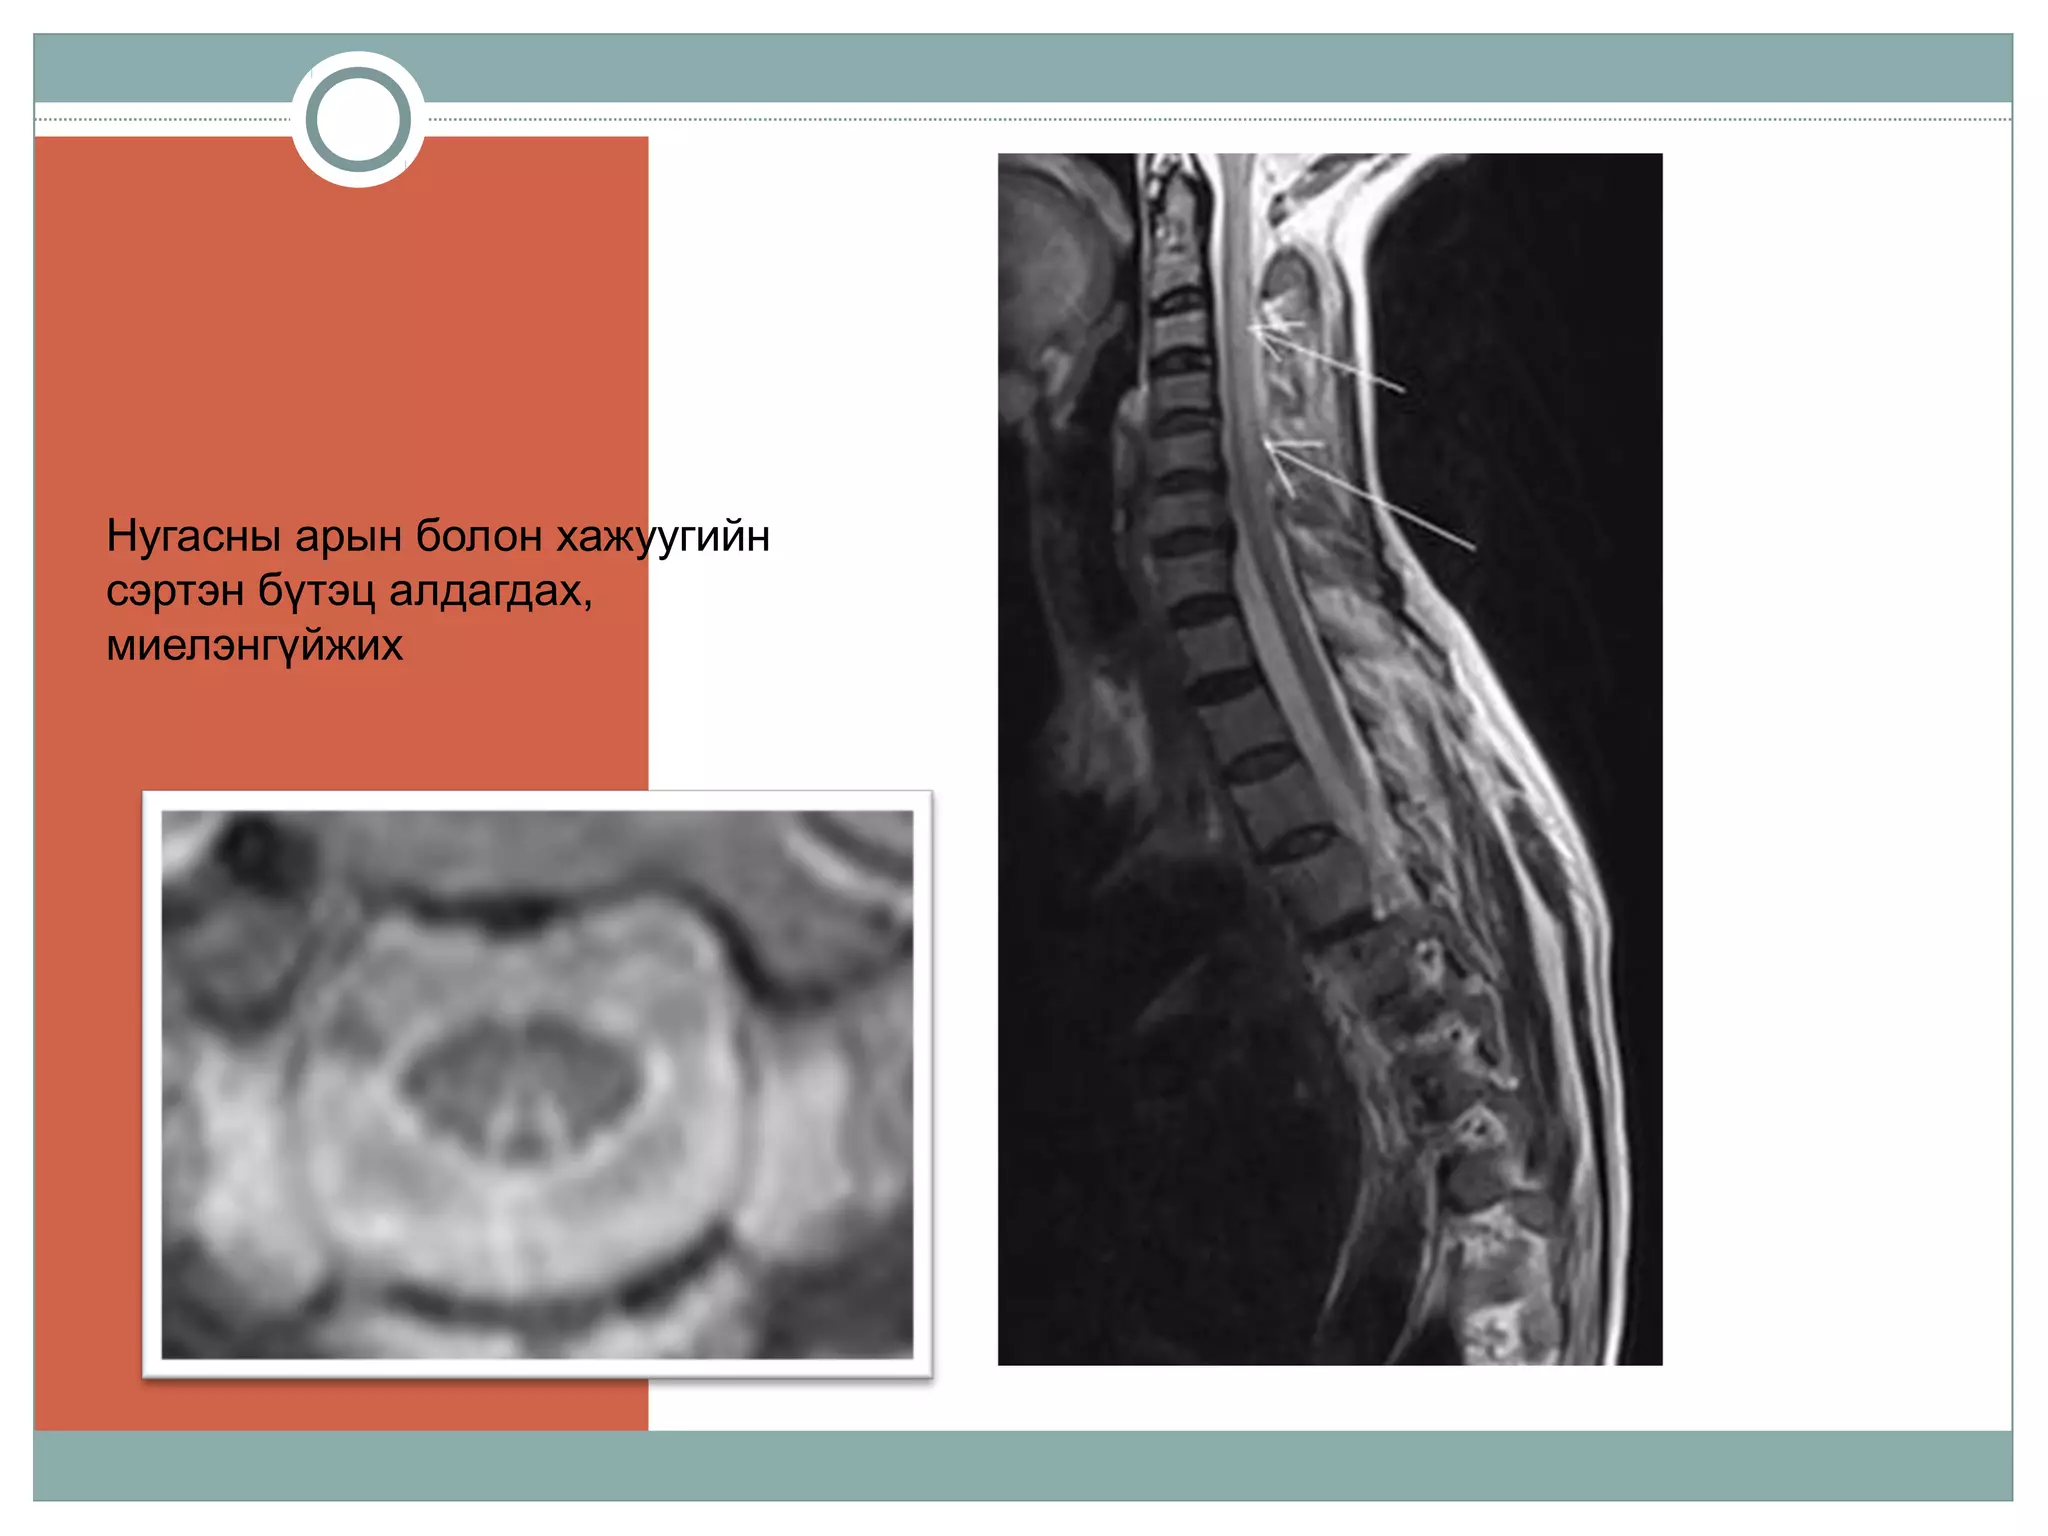

Нугасны арын болон хажуугийн

сэртэн бүтэц алдагдах,

миелэнгүйжих

Нугасны арын болонхажуугийн сэртэн бүтэц алдагдах, миелэнгүйжих